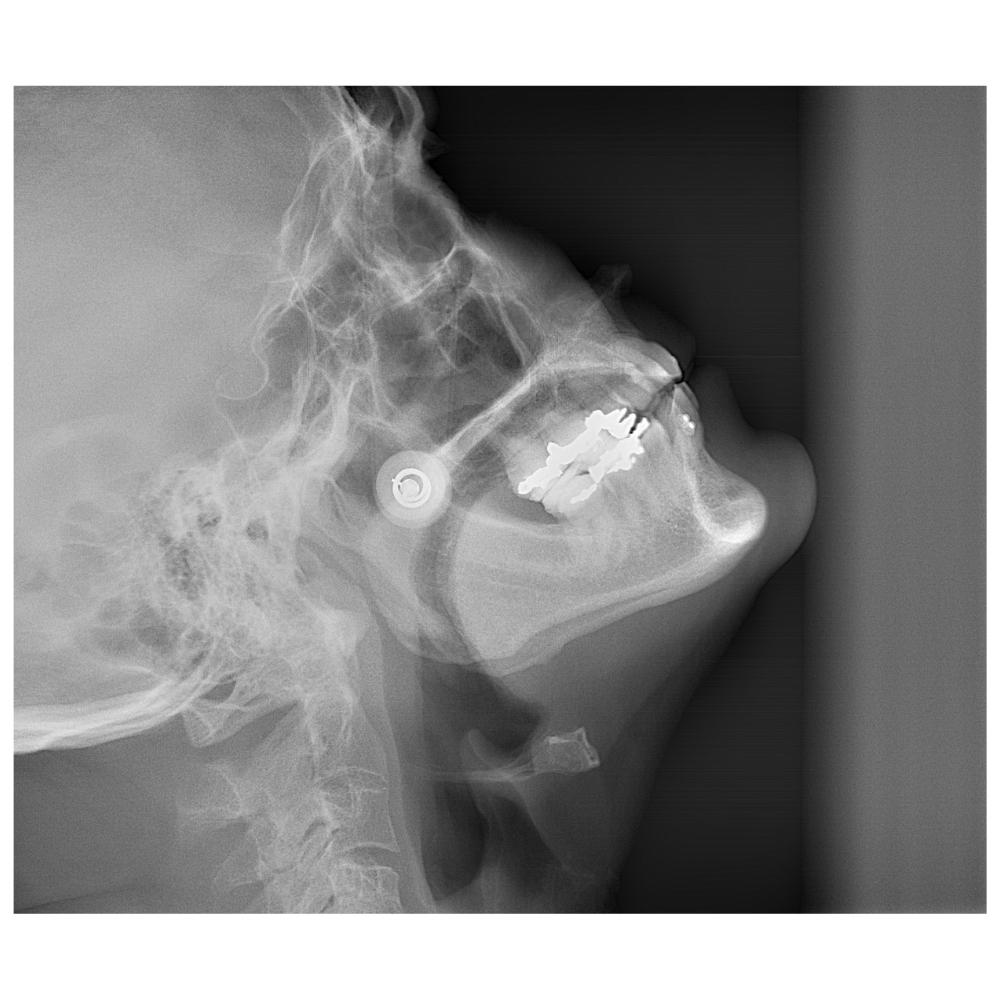

Descripción: Telerradiografía Lateral de Cráneo (Cefalometría) tomada con la cabeza del paciente en posición de extensión (inclinada ligeramente hacia atrás).

Propósito: Similar a la flexión, pero evalúa la influencia de la postura de extensión de la cabeza en la columna cervical y la mordida. Las vistas de flexión y extensión se usan para detectar inestabilidades.